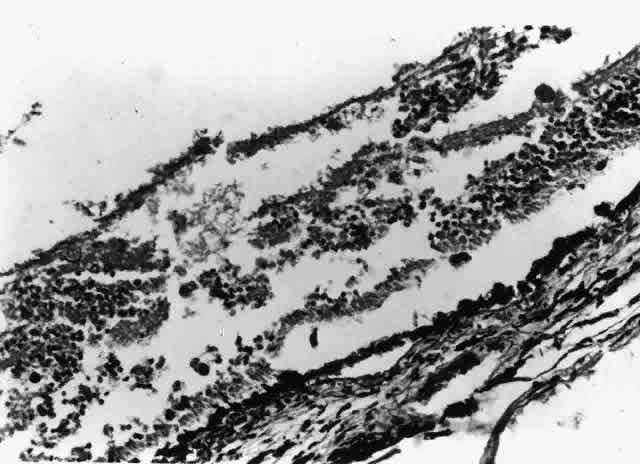

Cytomegalovirus (CMV) retinopathy is by far the most common of the severe ophthalmic infections in patients with AIDS. Varicella zoster virus retinopathy is being seen with increasing frequency; although it is probably the second most common retinal infection in North American HIV-infected patients, it is still far less common than CMV retinopathy. Toxoplasmic retinochoroiditis is the third retinal infection that is seen with some regularity, especially in certain areas of Europe and South America. The remaining retinal infections associated with AIDS are uncommon. They are seen with disseminated infections, in which the massive proliferation of organisms may overwhelm the patient's limited immune defenses. They are usually seen late in the course of the syndrome; thus, they may actually signal further waning of immune defenses. Patients with intraocular infections should be suspected of having tissue-invasive infections involving other internal organs. When they do occur, intraocular infections are frequently extensive and severe. Infections of the cornea and external eye are less common in HIV-infected individuals than intraocular infections. The natural defenses of normal eyelid function, tear film, and an intact corneal epithelium protect against many exogenous pathogens. It is therefore important that factors that might compromise those defenses, such as epithelial defects or trichiasis, be corrected as soon as possible. Also, HIV-infected patients who wear contact lenses should adhere strictly to lens care and disinfection techniques. Many HIV-infected individuals appear to have decreased aqueous tear production, which leads to feelings of dryness and irritation but does not seem to result in an increased incidence of ocular surface infections. At greater risk are patients who have permanent damage to the eyelids from zoster ophthalmicus, neurotrophic corneas from herpetic infections, or damage to the ocular surface from cicatricial conjunctivitis, similar to that of Stevens-Johnson syndrome, which is seen occasionally in patients with AIDS. HIV infection and its sequelae are being studied in a variety of animal models. Rhesus monkeys infected with simian immunodeficiency virus develop an AIDS-like illness. In this model the monkeys develop a variety of ophthalmic lesions, including CMV infections of the retina.10 This model may be useful for future studies of AIDS-related ophthalmic infections. CYTOMEGALOVIRUS Cytomegalovirus retinopathy is the most thoroughly studied of the ophthalmic manifestations of HIV infection. CMV retinopathy is an AIDS-defining index disease. Most studies have concentrated on treatment, but a great deal has been learned about the natural history of CMV retinopathy during the course of these studies. Cytomegalovirus is a ubiquitous DNA virus of the herpes group. Most of the adult population has been infected with CMV, but in most cases it does not cause any clinically apparent disease. The virus remains in the body, however, as a latent infection. In patients with AIDS, CMV can cause life-threatening infections involving many tissues, including the brain, lungs, and gastrointestinal tract. The reported prevalence of CMV retinopathy varies from 4% of ambulatory patients (primarily intravenous drug abusers)11 to 34% of eyes in an autopsy series of male homosexuals.9 This discrepancy may reflect the fact that CMV retinopathy occurs late in the course of AIDS. Most investigators believe that the true prevalence of CMV retinopathy among patients with AIDS is approximately 15% to 25%. It has been suggested that CMV retinopathy is more common in homosexuals, because of different levels of exposure to CMV between risk groups.11,12 Cytomegalovirus retinopathy is clearly a disorder of immunosuppressed persons. Prior to its association with AIDS, the infection in adults was seen almost exclusively in patients with defects in cellular immunity related to disease or immunosuppressive drugs.13,14 A single report of CMV retinopathy in a healthy adult was not confirmed by culture or tissue examination.15 There is no obvious correlation between the development of CMV retinopathy and levels of CMV antibodies. CMV retinopathy has been reported in the absence of detectable antibodies.16 Histologic studies of AIDS-related CMV retinopathy demonstrate the tissue necrosis and cytomegalic cells characteristic of all CMV infections (Fig. 1).9,17 Electron-microscopic and immunochemical studies have identified CMV viral particles and antigen in a patchy distribution throughout all layers of the retina and occasionally in contiguous retinal pigment epithelial cells.9 Viral antigens are only rarely identified in the choroid.9,18 Viral antigen in the choroid has been found in association with vessels and is not always adjacent to areas of retinopathy, suggesting that the virus reaches the choroid through independent hematogenous spread rather than by extension of infection from the retina. Among cases of AIDS examined at autopsy, 22% to 50% of those with CMV retinopathy have neutrophilic infiltrates in retinal tissue.9,19 This finding is atypical when compared with CMV retinopathy in non-AIDS patients, in which only a sparse lymphocytic infiltrate is observed. The difference has been attributed to intact granulocyte function and chemotaxis in patients with AIDS, in contrast to infants, organ transplant recipients, and patients with malignancies who can have more severe quantitative or qualitative granulocyte dysfunction.9 It has been noted that patients on immunosuppressive drugs can develop marked inflammatory reactions to CMV retinopathy when such drugs are withdrawn.14 Acute inflammatory cells may extend into the adjacent choroid despite the absence of identifiable viral antigens.9 The vitreous usually remains remarkably free of inflammatory material, despite the presence of virus in the vitreous cavity.20 A variety of stimuli (CMV antigen, immune complex deposition, and tissue necrosis) may be responsible for the production of chemotactic factors leading to neutrophilic infiltration. Immunochemical studies have revealed deposition of IgG, IgA, and, to a lesser extent, IgM and C3c in retinal tissue and within retinal arteriolar walls.9 Many IgA-bearing plasma cells were present in one case.17 Perivascular infiltration of neutrophils occurs, consistent with immune complex-mediated vasculitis,9,17 but there is poor correlation between the distribution of tissue-bound immunoglobulins, acute inflammatory cells, and CMV antigens.9 Thus, it is also possible that concurrent retinal infection with other as-yet-unidentified pathogens is responsible for the acute inflammatory reaction seen in these eyes. Inflammatory cell products do not appear to play a significant role in the extensive tissue destruction common to all cases of CMV retinopathy. The histopathologic characteristics of AIDS-related CMV retinopathy in one autopsy study are listed in Table 3.9 CMV retinopathy frequently begins adjacent to retinal vessels in the posterior pole (Fig. 2). It is believed that virus reaches the eye via the bloodstream. Untreated CMV retinopathy in patients with AIDS is a relentlessly progressive disease. Usually, infection begins with an isolated focus of disease; rarely are there more than two or three discrete areas of infection within the eye. These lesions invariably enlarge to involve additional retinal tissue. New lesions develop less frequently. The enlargement of lesions does not progress at the same rate from all lesion borders.21 The rate of progression is faster in an anterior direction toward the ora serrata than in a posterior direction toward the fovea. CMV retinopathy has been considered a “foveal-sparing” disease. In a series of organ transplant patients with CMV retinopathy reported by Egbert and associates prior to the AIDS epidemic, only 3 of 21 eyes had macular involvement.14 The higher incidence of macular involvement in early autopsy series of patients with AIDS may reflect the fact that progression of CMV retinopathy into the macular region could not be stopped prior to the introduction of ganciclovir and foscarnet therapy. Even though the fovea can eventually be destroyed, it is usually the last area to become infected; in some cases the disease appears to move circumferentially around the fovea (Fig. 3). Eventually the entire retina will be destroyed, usually within a 6-month period.19 Progression of the retinopathy halts abruptly at the ora serrata.9 Following total retinal necrosis, it is replaced by a thin gliotic membrane.19 No virus can be identified in ocular tissue at this late stage.